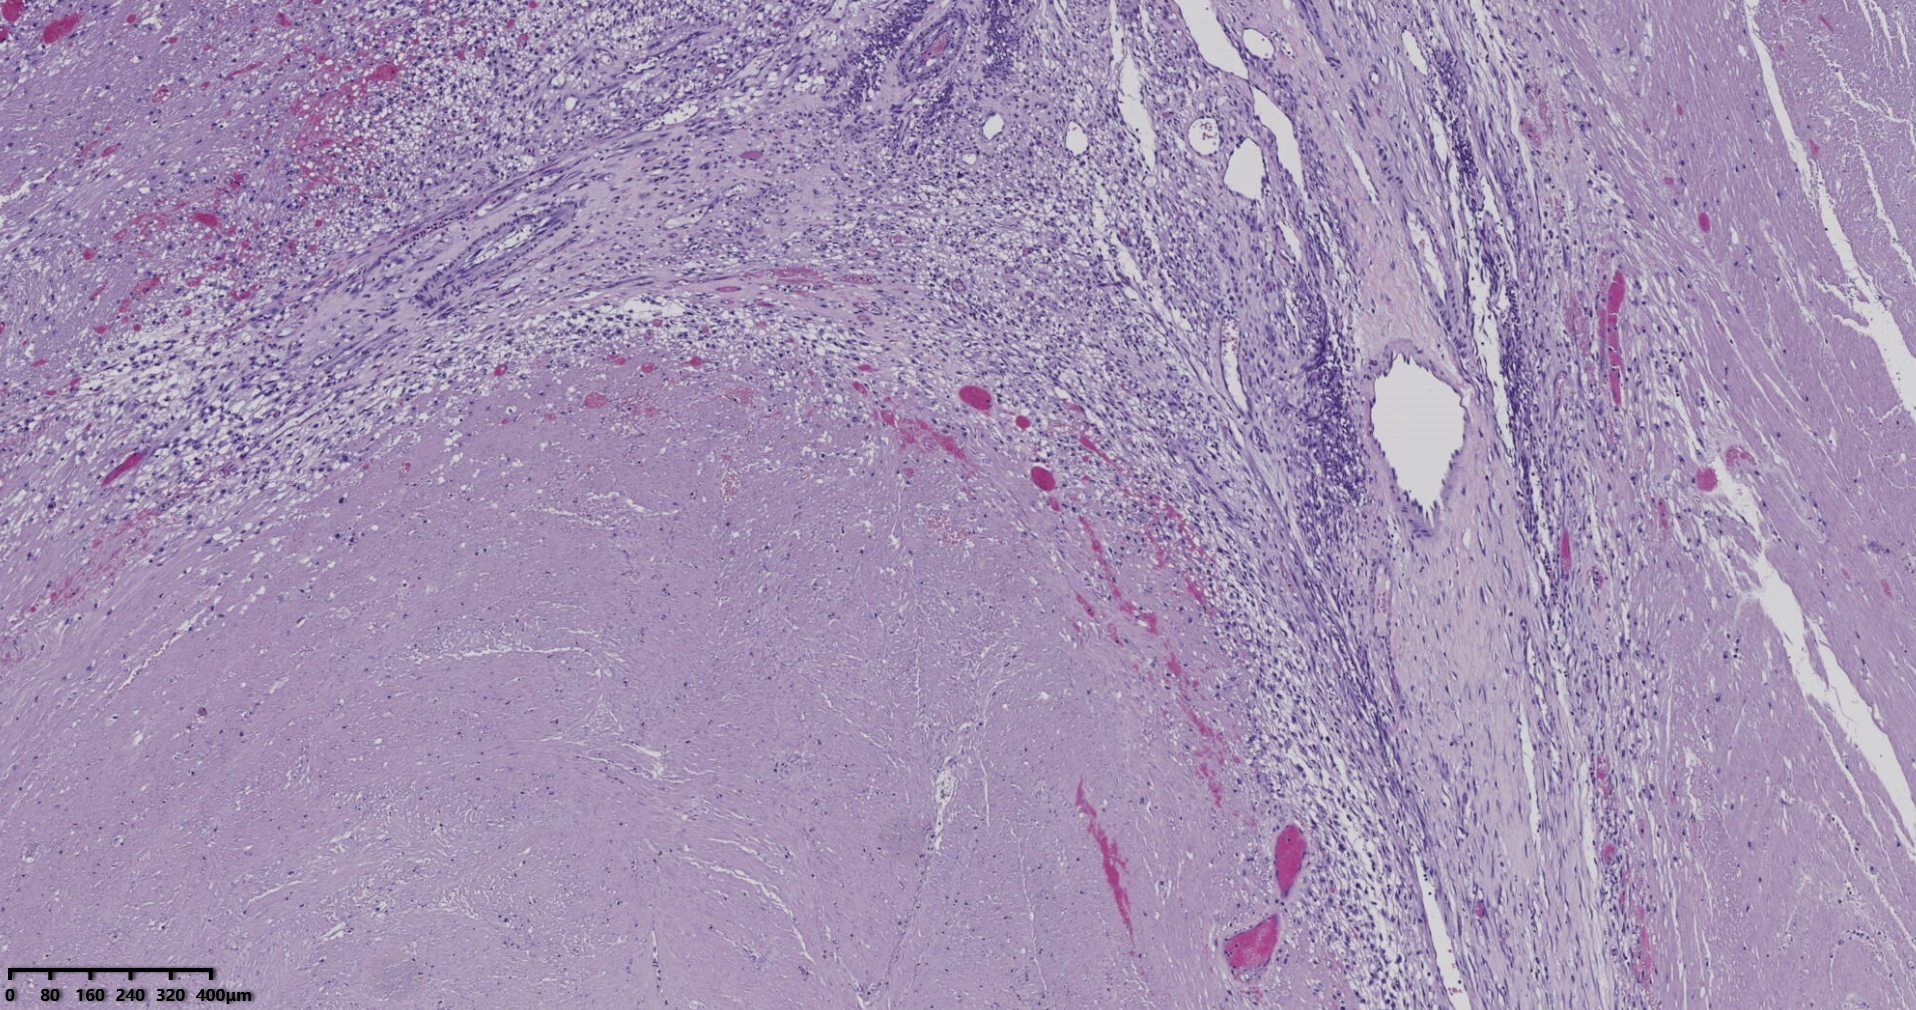

送检灰白肿物十余个,直径多在2-3厘米,切面均为灰白、实性,质地韧,其中一个大肿物,直径约7厘米,切片灰白灰红,质地韧当时取材时印象还是平滑肌瘤,伴变性,不考虑肉瘤,因为形态规整,质地韧,不脆,切面灰白,不是灰黄。

镜下所见小肿物无特殊,大肿物瘤细胞密集,中心区有变性、坏死,瘤细胞核有异型性。大肿物补充取材,发现,部分区域切面灰黄,这个区域,瘤细胞更密集,异型性更显著。肿物边缘有薄层正常平滑肌组织被覆,靠近边缘瘤细胞最密集,局部瘤组织内小血管较丰富。

会诊:考虑平滑肌肉瘤。

北医三院会诊:子宫平滑肌瘤伴红色变性可能性大,建议加做免疫组化及NGS检测进一步明确诊断。